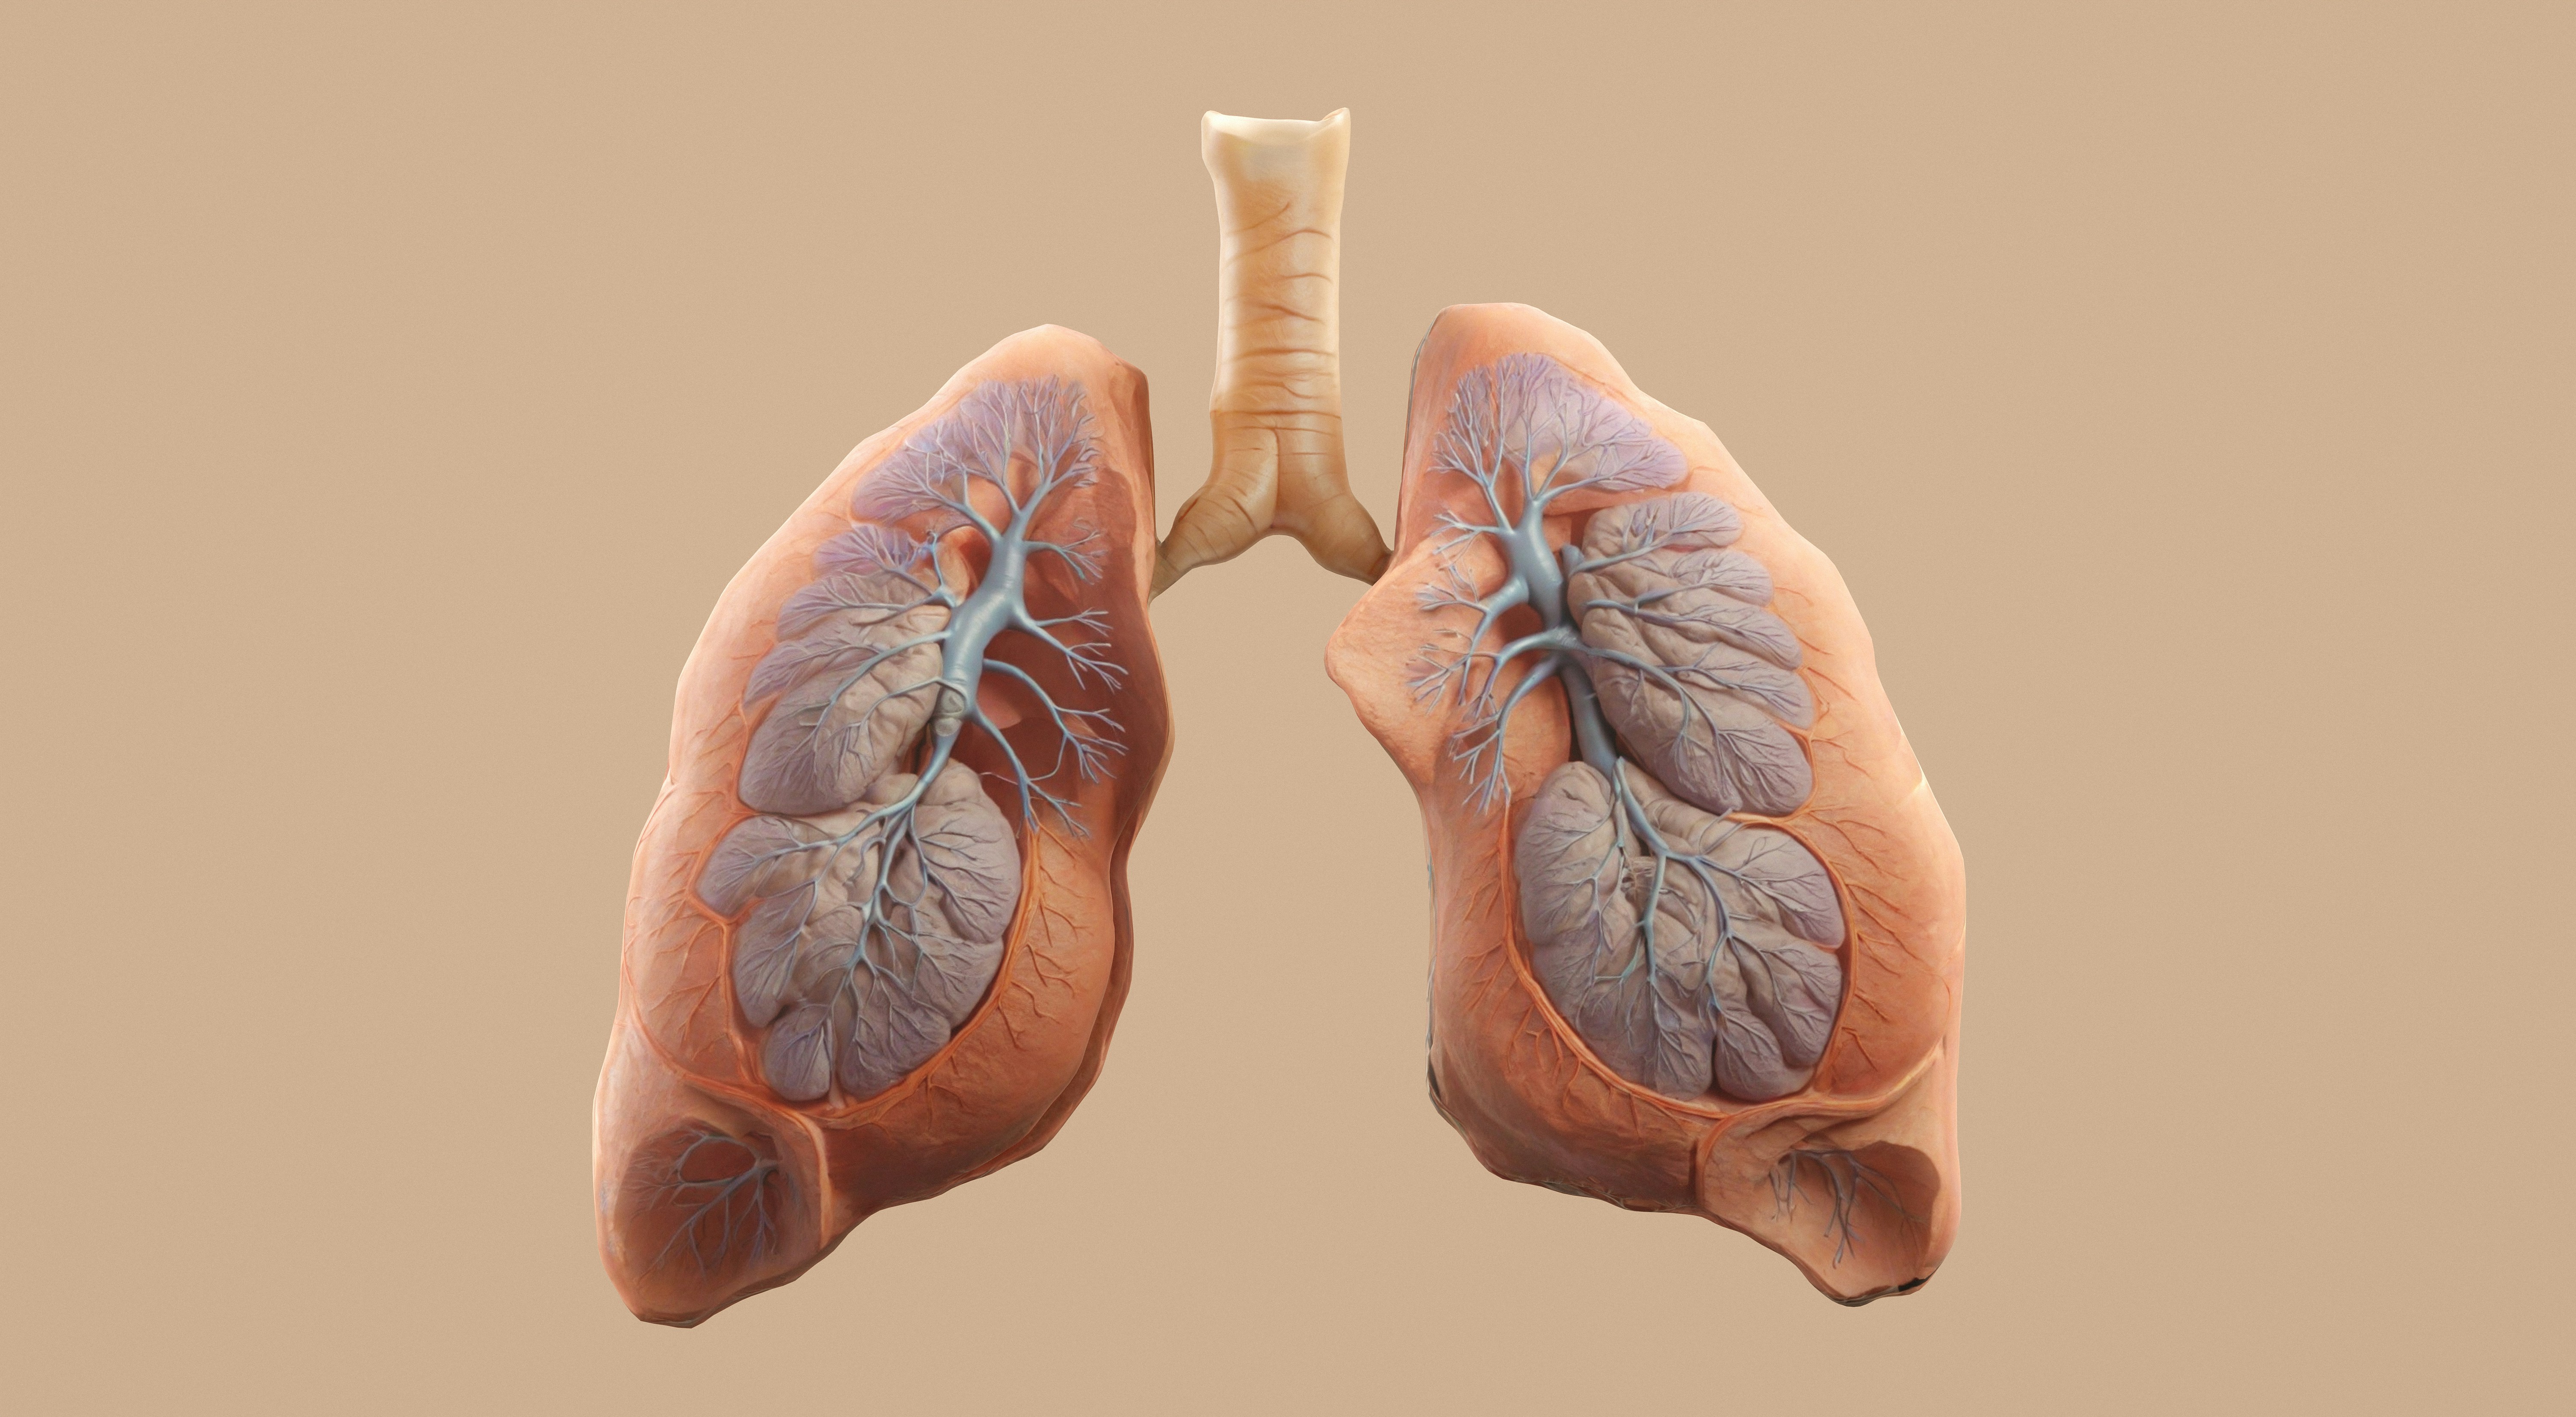

폐에 물이 차는 증상은 생각보다 많은 사람들이 겪을 수 있는 심각한 건강 문제입니다. 갑자기 숨이 가쁘고 가슴이 뻐근해지는 경험, 혹시 있으신가요? 단순한 피로나 감기라고 생각하고 넘기기엔 치명적인 병의 신호일 수 있습니다. 저 역시 처음엔 숨이 찬 증상이 단순한 컨디션 문제라고 생각했다가 큰 병원에서 "폐에 물이 차 있다"는 진단을 받고 깜짝 놀랐던 기억이 있습니다.

폐에 물이 차면 폐가 팽창하지 못하고 눌리기 때문에 숨을 들이쉬는 것 자체가 힘들어집니다. 이 때문에 사람들은 마치 계단을 몇 층이나 오른 듯한, 갑작스럽고 지속적인 숨참 증상을 경험하게 됩니다. 특히 밤에 누웠을 때 증상이 더 심해지는 경향이 있는데, 이는 수평 자세에서 폐에 물이 더 퍼지기 때문입니다.